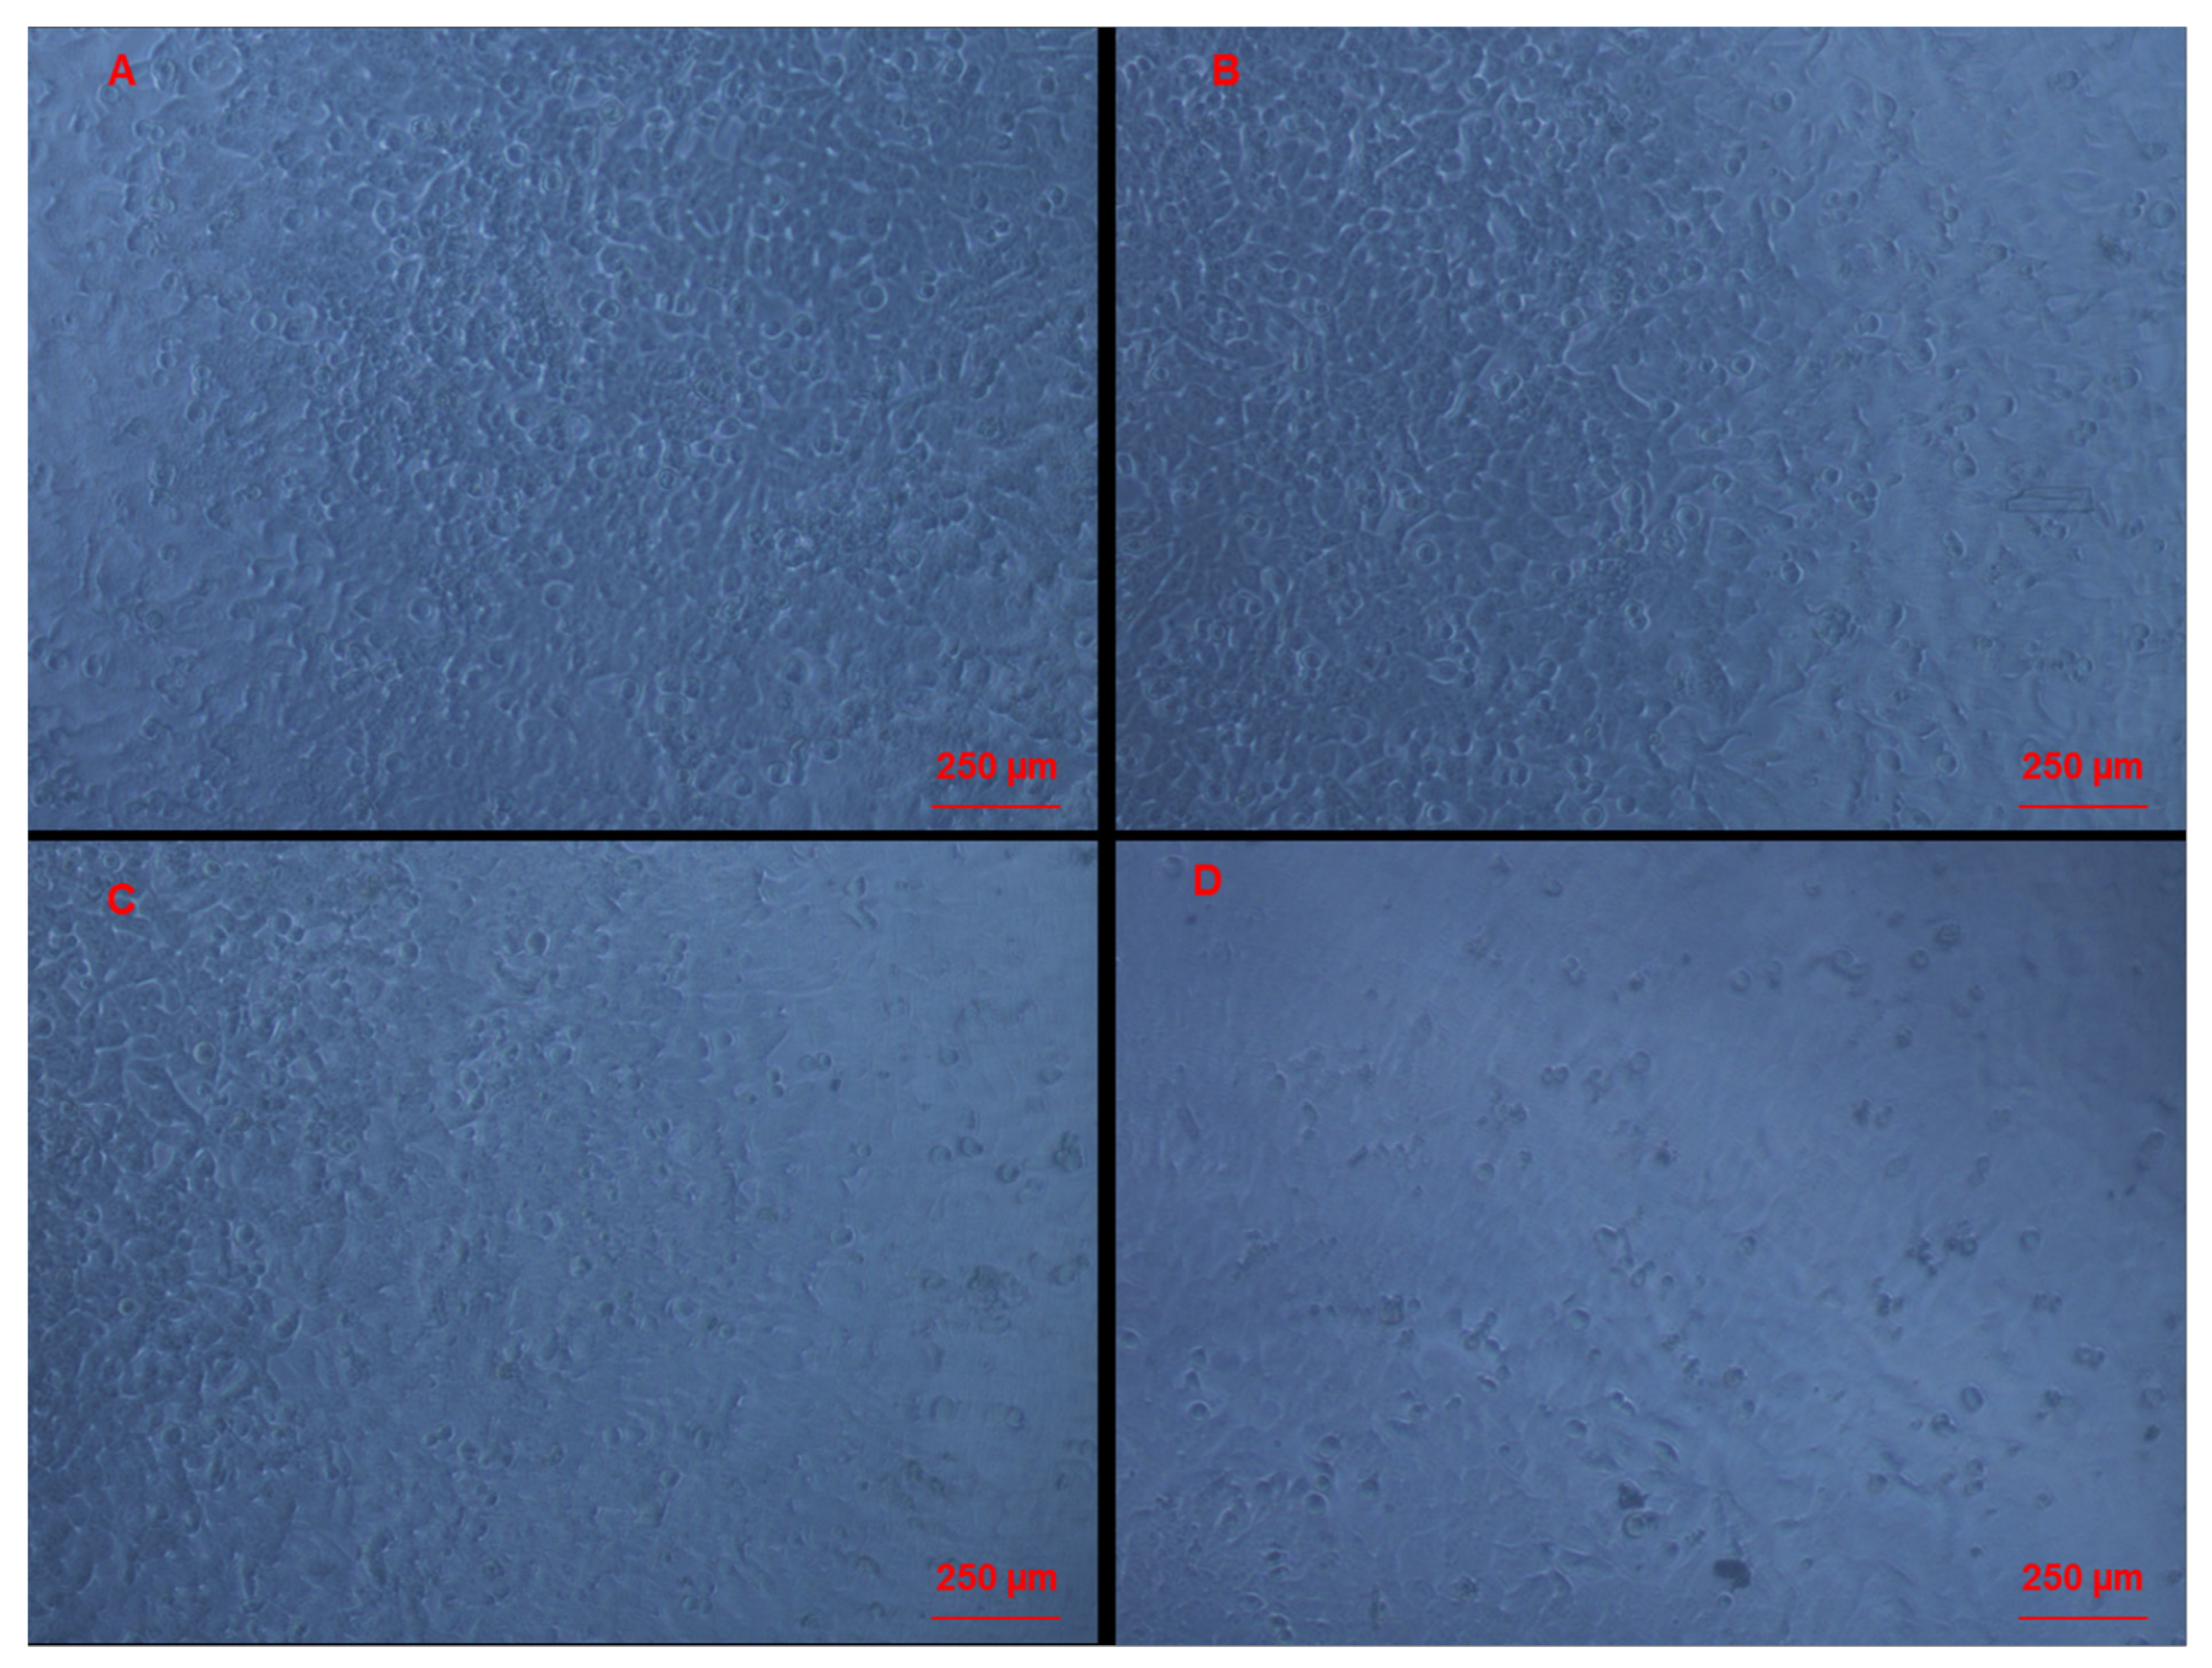

3.3. Morphological Changes of Caco-2 Cells Induced by CAII Treatment